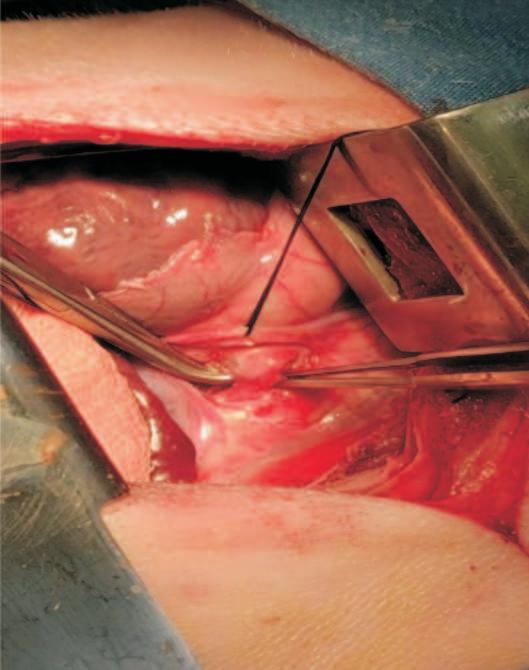

Se delimita el área quirúrgica con campos quirúrgicos estériles. El abordaje de la toracotomía izquierda se efectúa en el 4to. espacio intercostal, para lo que se diseccionan el músculo dorsal ancho, los serratos, el escaleno, los intercostales externos, los intercostales internos y la pleura parietal.

Actoseguido,seidentificaelmediastinocranealalcorazónysepreservaelnerviovago,elcualseretirahaciaventral,con suturatemporaldeseda.Unaveziniciada

Se identifica el conducto arterioso permeable, se emplea una pinza Mixter de 16 cm (Figura 2), este procedimiento requiere de un manejo preciso y delicado paraevitardañarlaarteriapulmonar,misma que se encuentra por abajo y atrás de laaortaenelsitioanatómicodelconducto arterioso12 (Figuras 3-7).

Finalmente,sehacepasardoshilosde sutura de seda calibre 2-0 alrededor del conducto arterioso, mismo que se liga en el extremo dorsal (cerca de la aorta) y en el extremo ventral (proximal a la arteria pulmonar) para ser cortado entre ambas ligaduras, se revisa la ausencia de hemorragia (Figuras 8-11). En los monitoresseidentificancambiosdePVC y PA, sin mayor relevancia, se procede al cierre de la cavidad.